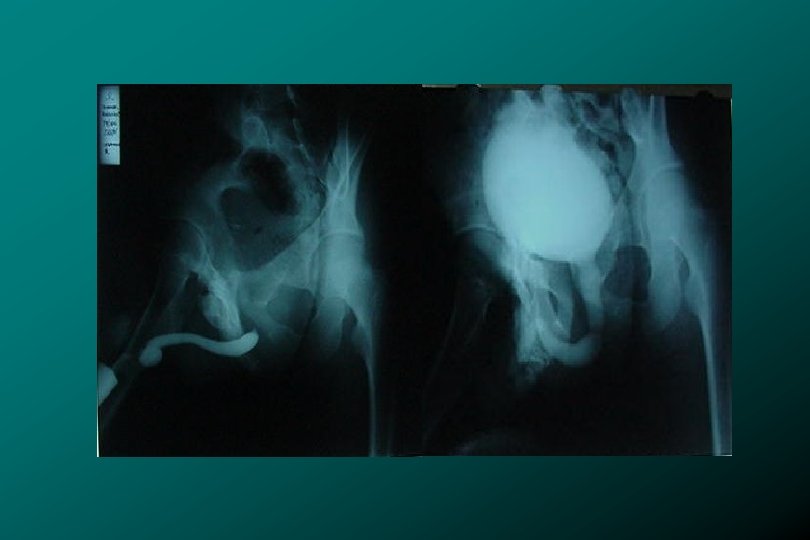

TRAUMA DE URETRA POSTERIOR CLASIFICACIÓN * Tipo II Ruptura uretra prostatomembranosa (17%). * Zegarra

TRAUMA DE URETRA POSTERIOR CLASIFICACIÓN * Tipo II Ruptura uretra prostatomembranosa (17%). * Zegarra L. : Traumatismos Urológicos. En: Barboza ed. Principios y Terapéutica Quirúrgica. Lima: De Arteta Imp. 1999: 576 -590.

TRAUMA DE URETRA POSTERIOR CLASIFICACIÓN * Tipo III (66%) Ruptura uretra prostatomembranosa Ruptura de

TRAUMA DE URETRA POSTERIOR CLASIFICACIÓN * Tipo III (66%) Ruptura uretra prostatomembranosa Ruptura de Diafragma urogenital. Lesión de uretra bulbar * Zegarra L. : Traumatismos Urológicos. En: Barboza ed. Principios y Terapéutica Quirúrgica. Lima: De Arteta Imp. 1999: 576 -590.